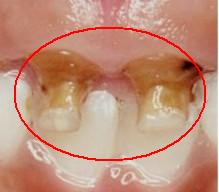

Código 6

(Caries Severa ): Cavidad

detectable extensa con dentina visible más de la mitad de la superficie

- Cavidad extensa detectable con dentina visible, que

ocupa más de la mitad de la superficie dental ó la pulpa

(los códigos 6 son profundos y amplios)

- No es conveniente utilizar una sonda periodontal, para

determinar la dureza del tejido cariado.